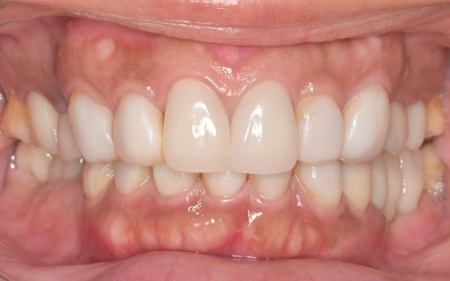

治療後

上顎の前歯2本ずつと奥歯4本(左右中切歯・第2小臼歯・第1大臼歯)、下顎の奥歯7本(左第1小臼歯・左右第2小臼歯・第1大臼歯・第2大臼歯)には、見た目が自然なセラミックの被せ物「ジルコニアクラウン」を装着しました。

ジルコニアは、金属を使わないため金属アレルギーの心配が少ない点、人工ダイヤモンドと呼ばれるほどの強度をもち噛む力の強い奥歯にも適している点がメリットです。

加えて、上前歯4本(左右側切歯・犬歯)と下前歯5本(左右中切歯・側切歯・右下犬歯)は、ダイレクトクラウンによる修復を行いました。

ダイレクトクラウンとは、レジン(樹脂)を用いて直接歯の形を作り上げていく治療方法です。

歯を削る量が少ない、色や形を細かく調整しながら仕上げられる、治療後は必要に応じて微調整がしやすいなどのメリットがあります。

最後に、見た目や噛み合わせに問題がないかを確認し、治療を終了しました。